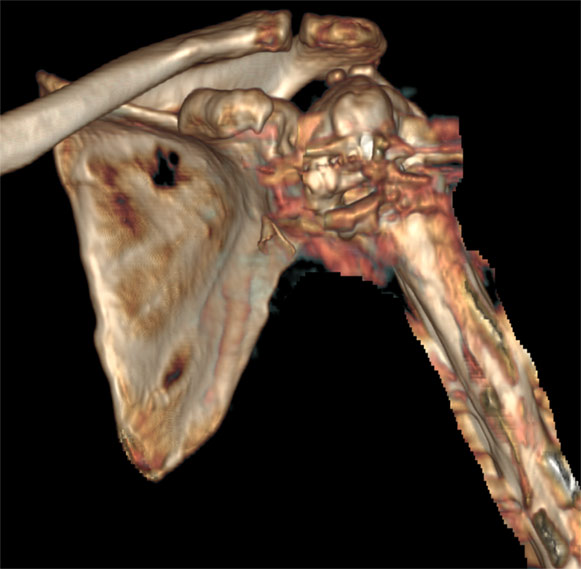

În final, pentru a veni în ajutorul medicului radiolog sau ortoped, examinarea trebuie să se încheie cu o reconstrucție 3D, cel mai frecvent de tip VRT (volume rendering), care să permită rotirea volumului de examinat în orice direcție și aprecierea suprafeței osoase și a traiectelor de fractura/ fragmentelor osoase din focar.

Image

Reconstrucție tridimensională a oaselor din articulația umărului (VRT)

Aspect de rotație în jurul axului a unei reconstrucții 3D

Reconstrucțiile se fac preferabil din secvențele cu fine (kernel de părți moi). Cele reconstruite din imaginile cu kernel de os sunt cu margini prea ascuțite.